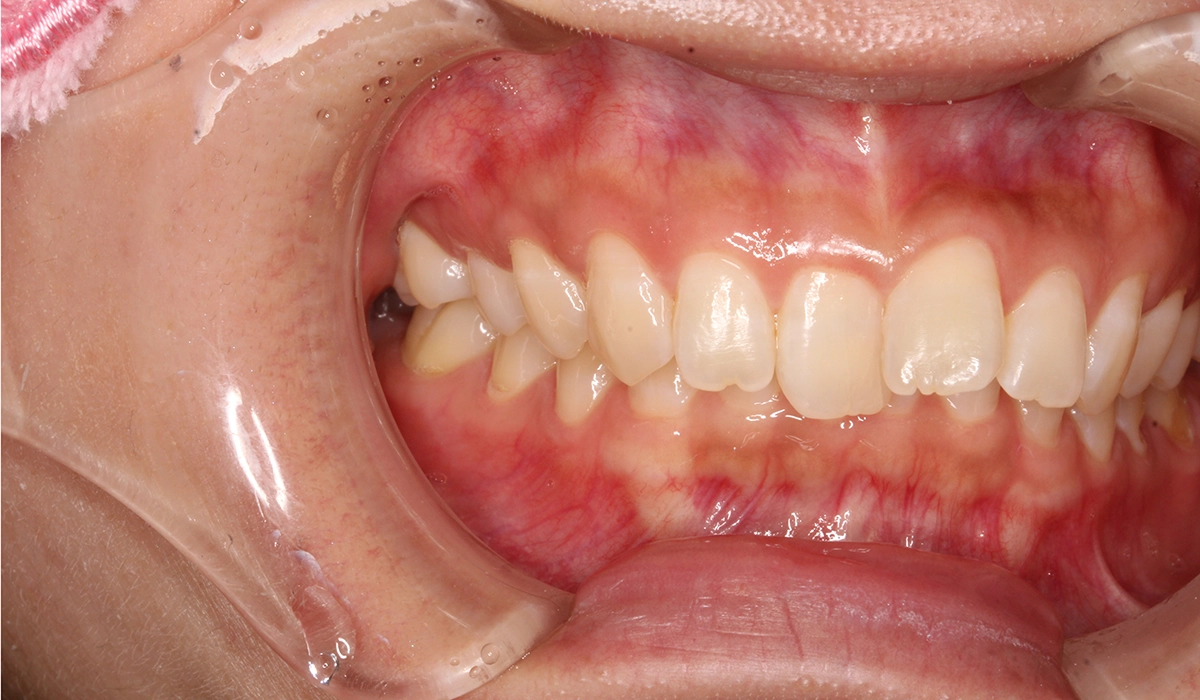

術前:右側

術後:右側